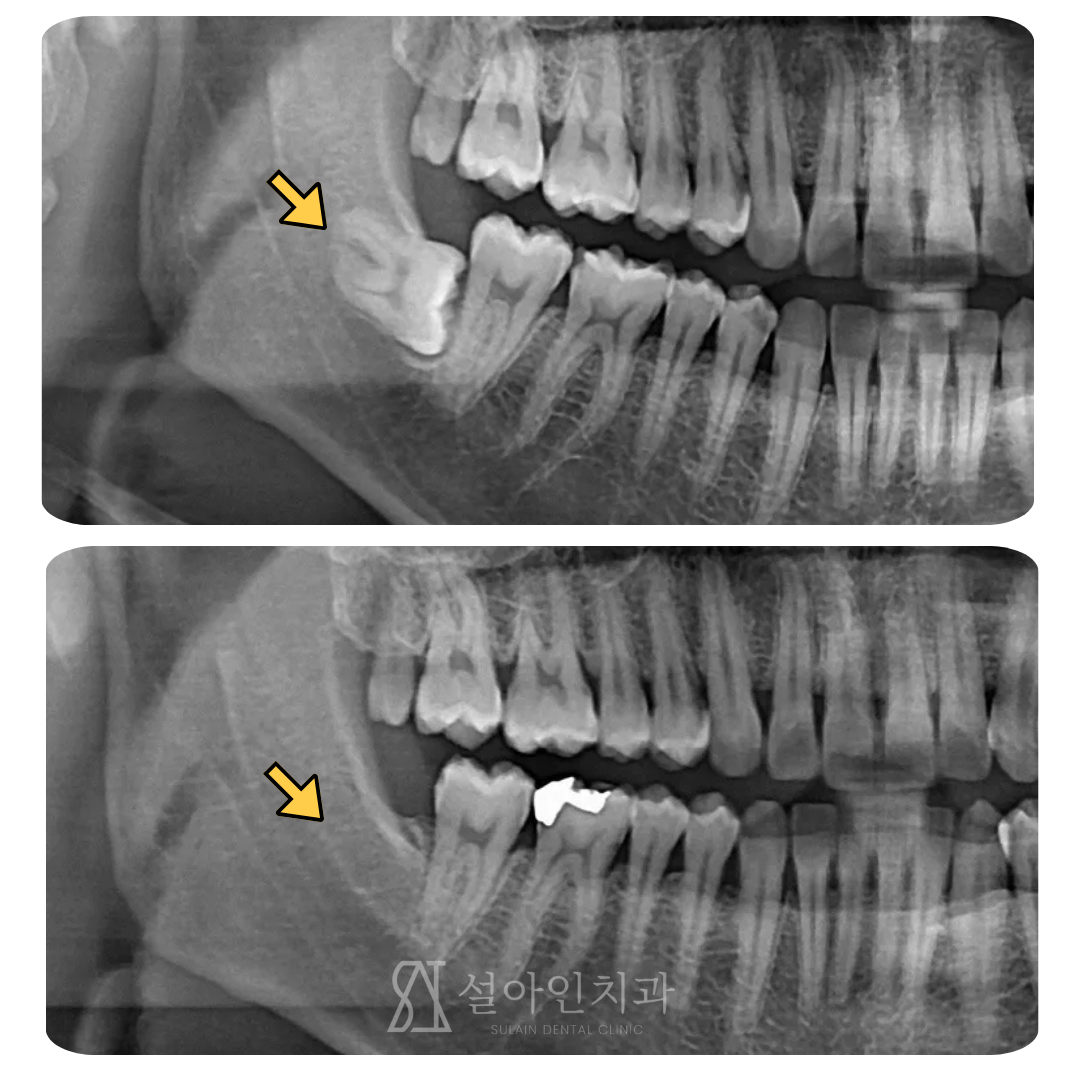

가로로 누워 자란 사랑니, 난이도 높은 수술도 안전하게 뽑을 수 있습니다.